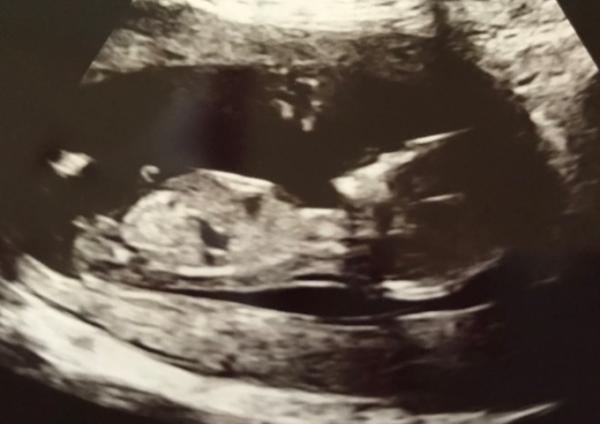

Hallo ihr Lieben, erkennt ihr den Nub? Falls ja, was denkt ihr? Wird es ein Junge oder ein Mädchen ? Ich bin sehr gespannt auf eure Einschätzungen!

Bild zu Nub Theorie- Wer erkennt etwas? - Baby Forum - Allgemeine Themen

Hallo Ich bin kein Experte aber ich würde auf junge tippen Schau mal ich füge dir mal ein Bild ein vllt hilft das auch etwas

Ich tippe auf einen Jungen Lg